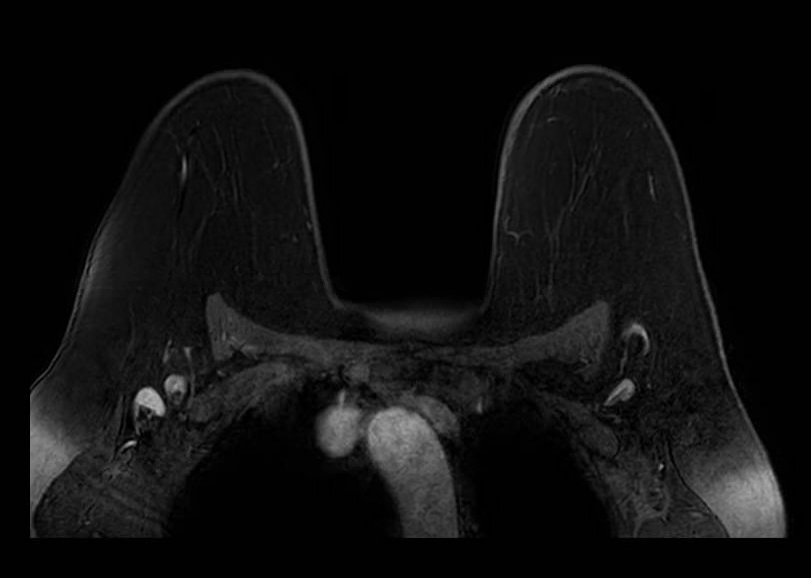

Fat Sat - Multi-slice Progression

Progression of fat suppression failure across image stack. Sequential axial fat-saturated T1-weighted images (A, B) from the same acquisition demonstrate how the extent of fat suppression failure varies across slices, worsening toward the periphery of the prescribed volume. This through-plane variability can mimic asymmetric background parenchymal enhancement if not recognized.